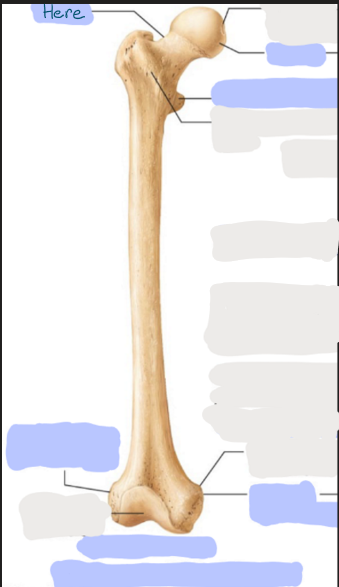

What is this picture of?

Anterior view of the Right Femur

What is here?

Where is the Neck of the Femur?

What is here?

Where is the Head of the Femur?

What is here?

Where is the Lesser Trochanter of the Femur?

What is here?

Where is the Lateral Epicondyle of the Femur?

What is here?

Where is the Medial Epicondyle of the Femur?